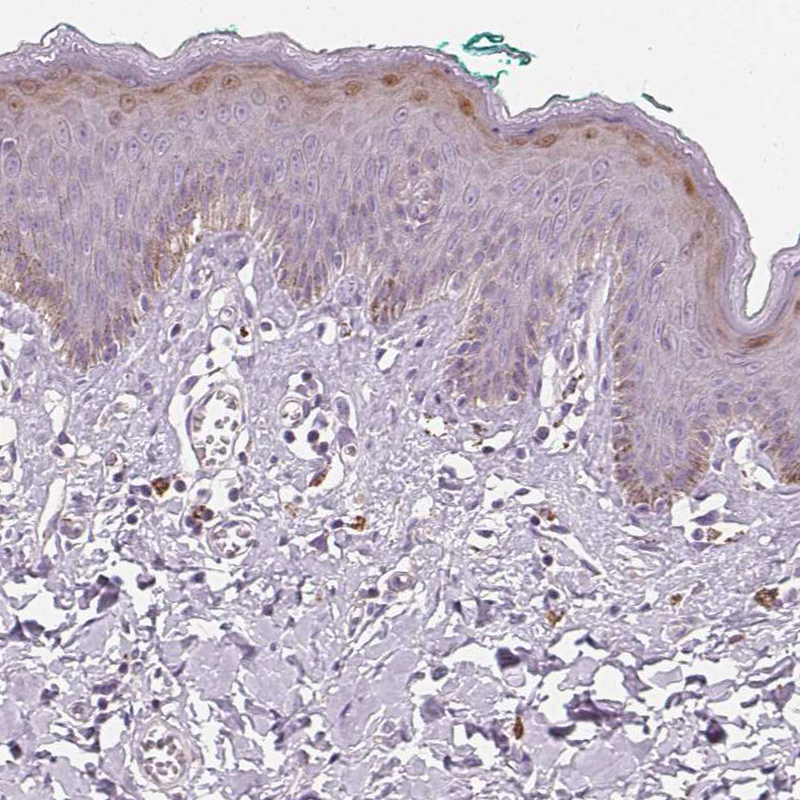

Immunohistochemistry analysis in human skin and liver tissues using HPA030180 antibody. Corresponding HOPX RNA-seq data are presented for the same tissues.